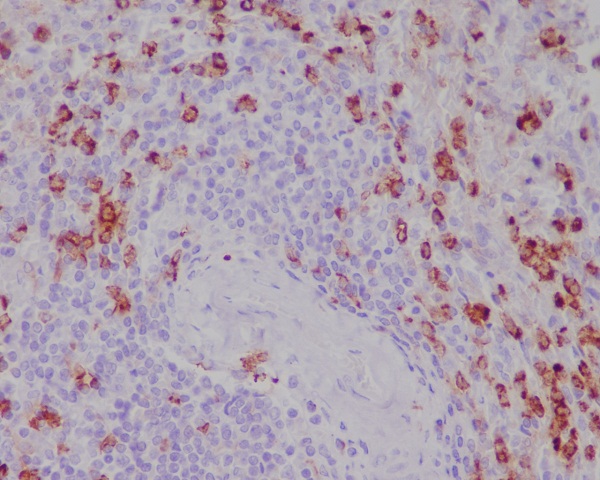

Immunohistochemical analysis of paraffin-embedded human spleen, using CD11b Antibody.